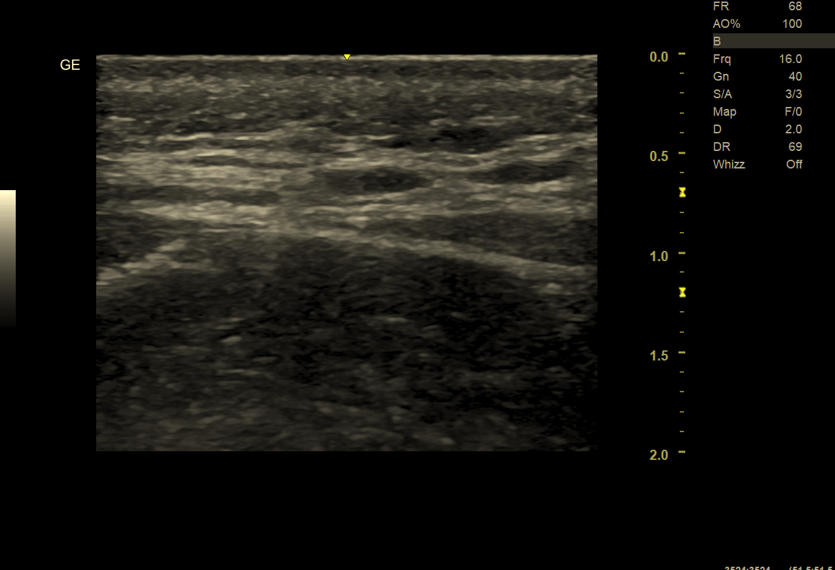

W przypadku nerwów obwodowych USG jest metodą pierwszego wyboru, pod warunkiem użycia:

- głowic o bardzo wysokiej częstotliwości (15–22 MHz),

- odpowiedniego doświadczenia badającego.